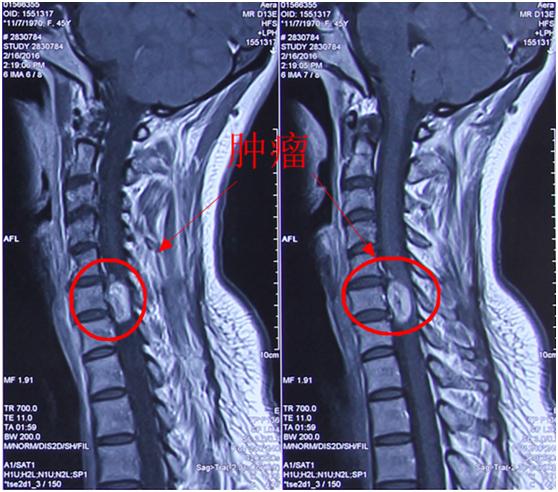

病例分享:成功全切10年病史患者高颈段神经鞘瘤

贺晓生教授枕颈交界区多发神经鞘瘤